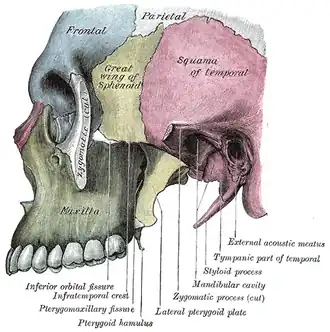

Вид сбоку. Верхняя челюсть в нижней левой части, обозначена зелёным. | |

У человека воздухоносная, так как в ней находится обширная полость — верхнечелюстная (гайморова) пазуха (sinus maxillaris). Имеет тело верхней челюсти (corpus maxillae), 4 отростка: лобный отросток (processus frontalis), альвеолярный отросток (processus alveolaris), небный отросток (processus palatinus), скуловой отросток (processus zygomaticus). Поверхности верхней челюсти: передняя поверхность (facies anterior), носовая поверхность (facies nasalis), подвисочная поверхность (facies infratemporalis), глазничная поверхность (facies orbitalis)[1].

- скуловой отросток (processus zygomaticus);